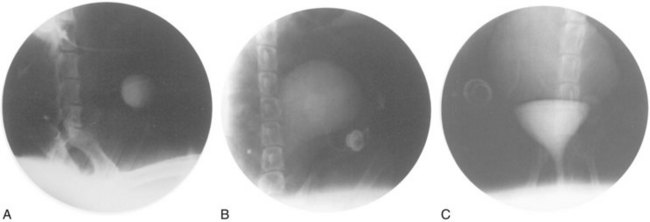

A system for the progressive expansion of native bladder tissue has also been used for augmenting bladder volumes (Satar et al, 1999). Beagle dog bladders were divided horizontally into two segments: a superior bladder neoreservoir, and an intact smaller bladder inferiorly with both ureters left intact and draining. A Silastic catheter was threaded into the newly formed, superiorly located neoreservoir and connected to an injection port, which was secured subcutaneously. Four weeks after surgery, a saline-antibiotic solution was injected daily into the palpable injection port, dilating the neoreservoir through the Silastic catheter. Within 30 days after progressive dilation, the neoreservoir volume was expanded at least 10-fold (Fig. 19–8). Urodynamic studies showed normal compliance in all animals, and microscopic examination of the expanded neoreservoir tissue showed a normal histology. A series of immunocytochemical studies demonstrated that the dilated bladder tissue maintained normal phenotypic characteristics (Satar et al, 1999).

Figure 19–8 Progressive bladder dilation can be performed with adequate increases in capacity. Cystography of bladder neoreservoir before progressive dilation (A) is compared with cystography results after progressive dilation (B) and with cystogram showing dilated neoreservoir and intact bladder segment (C).